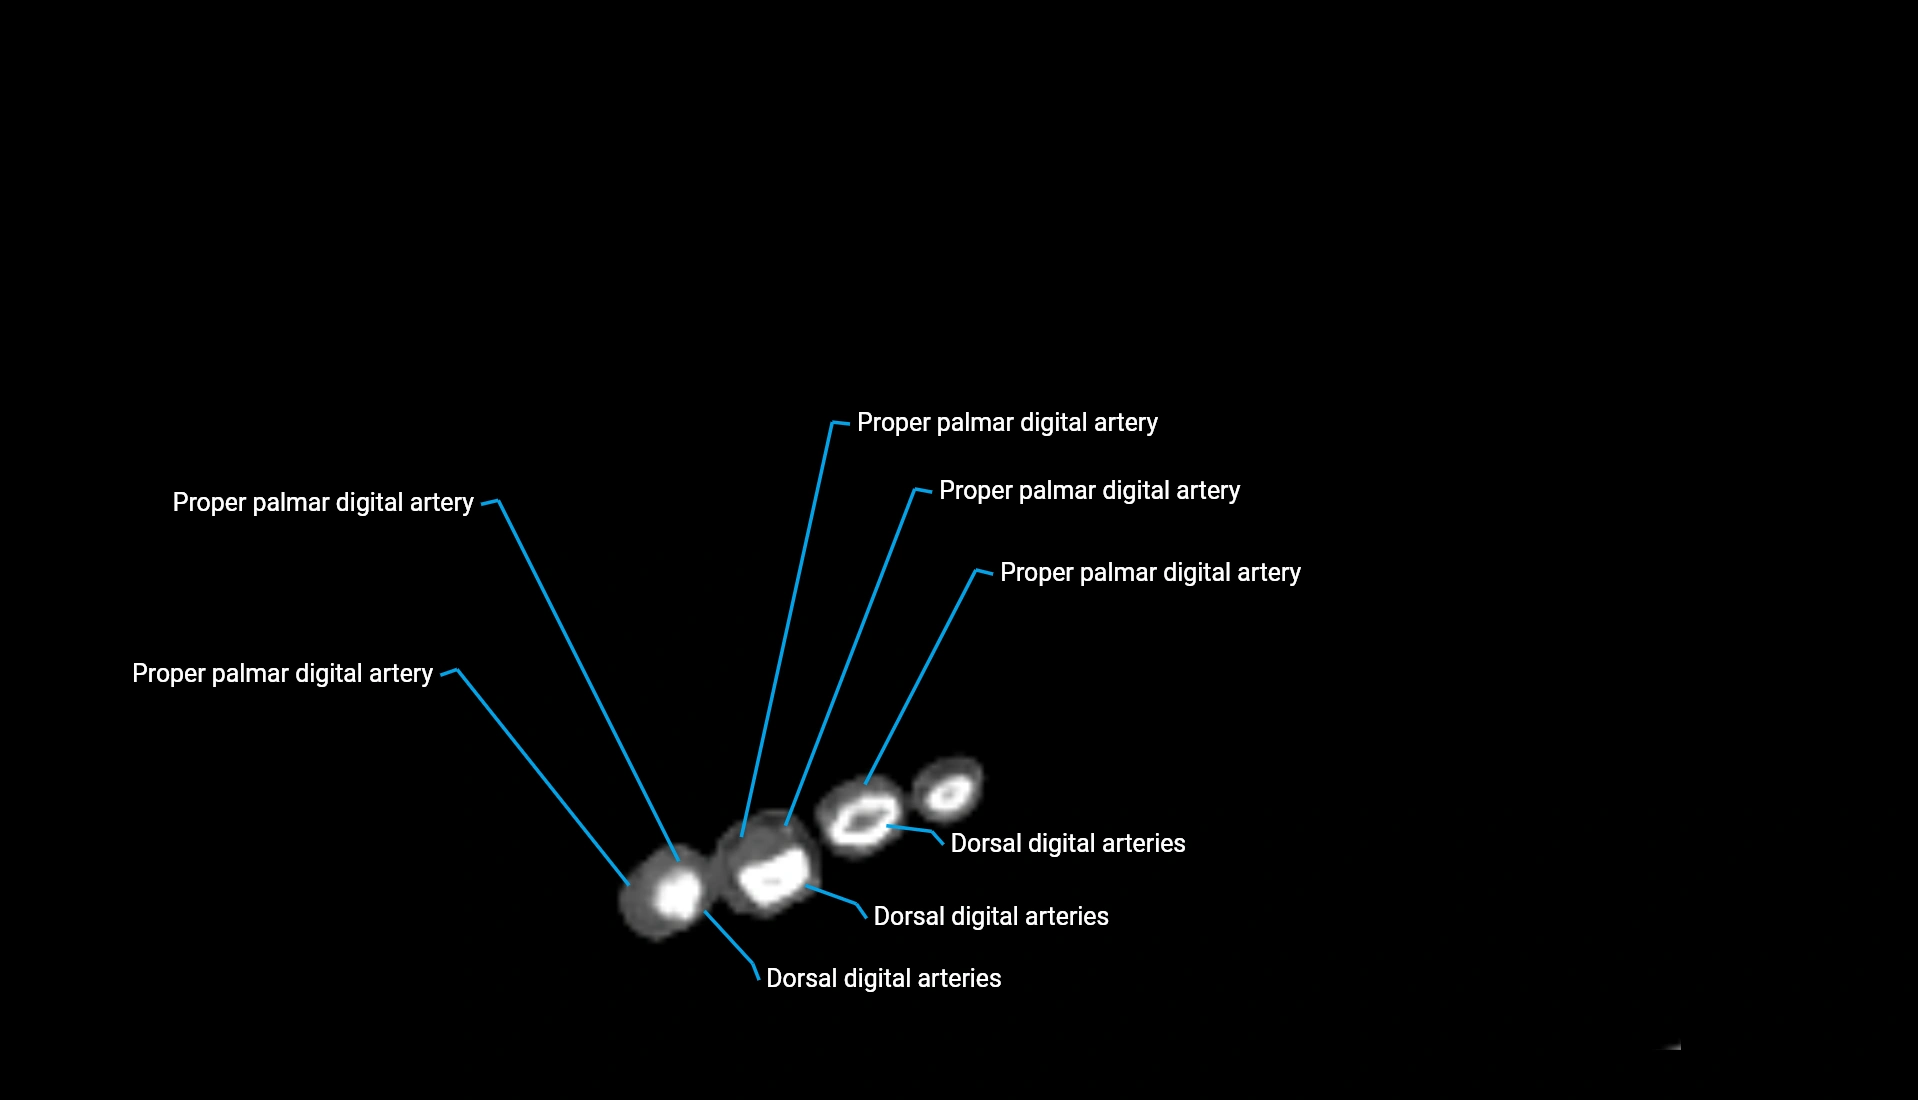

CT Appearance

Non-Contrast CT:

• Cortex: High-density, sharply defined

• Subchondral bone: Dense cancellous matrix

• Articular surface: Smooth concave contour articulating with the capitellum

• Excellent for evaluating bone integrity, alignment, and subtle fractures